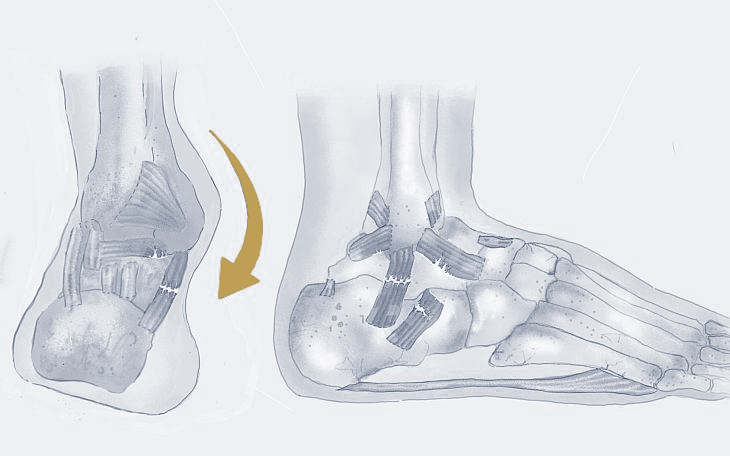

Bildquelle: www.docset.de

Symptome

Viele Menschen mit einem Plattfuß haben keine Beschwerden. Bei anderen können jedoch Schmerzen im Fuß, Knöchel oder Bein auftreten, insbesondere nach längerer Belastung. Auch eine Schwellung im Bereich des Innenknöchels, eine eingeschränkte Beweglichkeit des Fußes und eine schnelle Ermüdung können auftreten.

Ursachen

Die Ursachen können vielfältig sein. Angeborene Fehlbildungen, eine Schwäche des Bindegewebes, Übergewicht, falsches Schuhwerk, Überlastung, Verletzungen oder auch neurologische Erkrankungen können eine Rolle spielen.

Konservative Therapie

Das Tragen von stützenden Einlagen, die das Fußgewölbe anheben, Schuhe mit guter Unterstützung, Fußgymnastik zur Kräftigung der Fußmuskulatur, Gewichtsreduktion und entzündungshemmende Medikamente können die Beschwerden lindern.

Operative Therapie

In seltenen Fällen, wenn die konservativen Maßnahmen nicht ausreichend helfen und die Schmerzen den Alltag erheblich beeinträchtigen, kann eine Operation in Erwägung gezogen werden. Dabei werden je nach Ursache und Ausprägung des Plattfußes verschiedene operative Verfahren eingesetzt, um das Fußgewölbe wiederherzustellen und die Fehlstellung zu korrigieren.